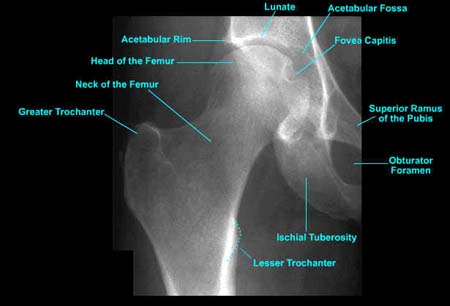

Hip joint AP image